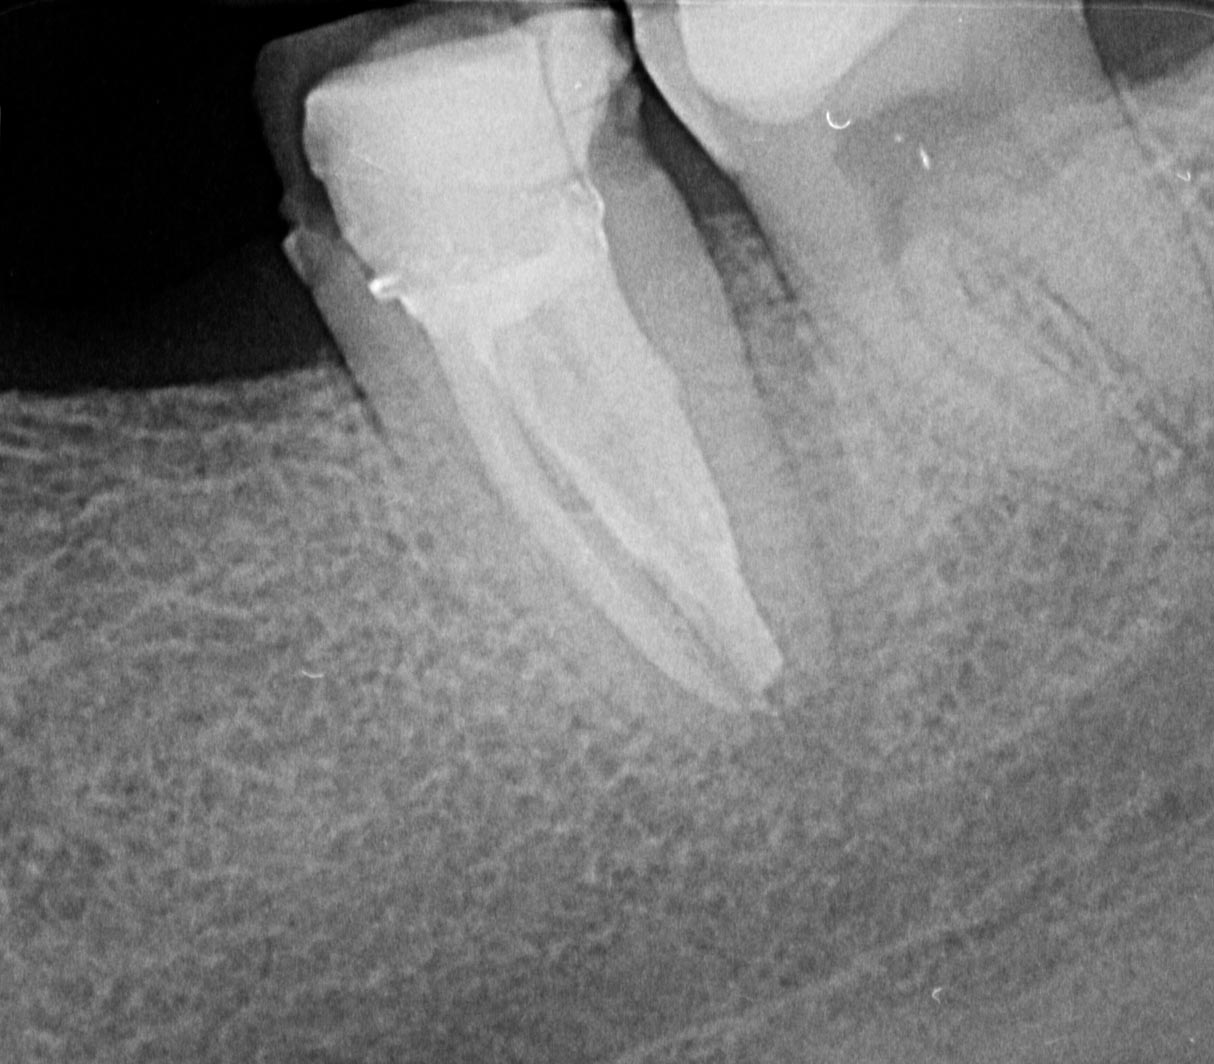

C Shape-5

1214 × 1064

C Shape Zahn 37